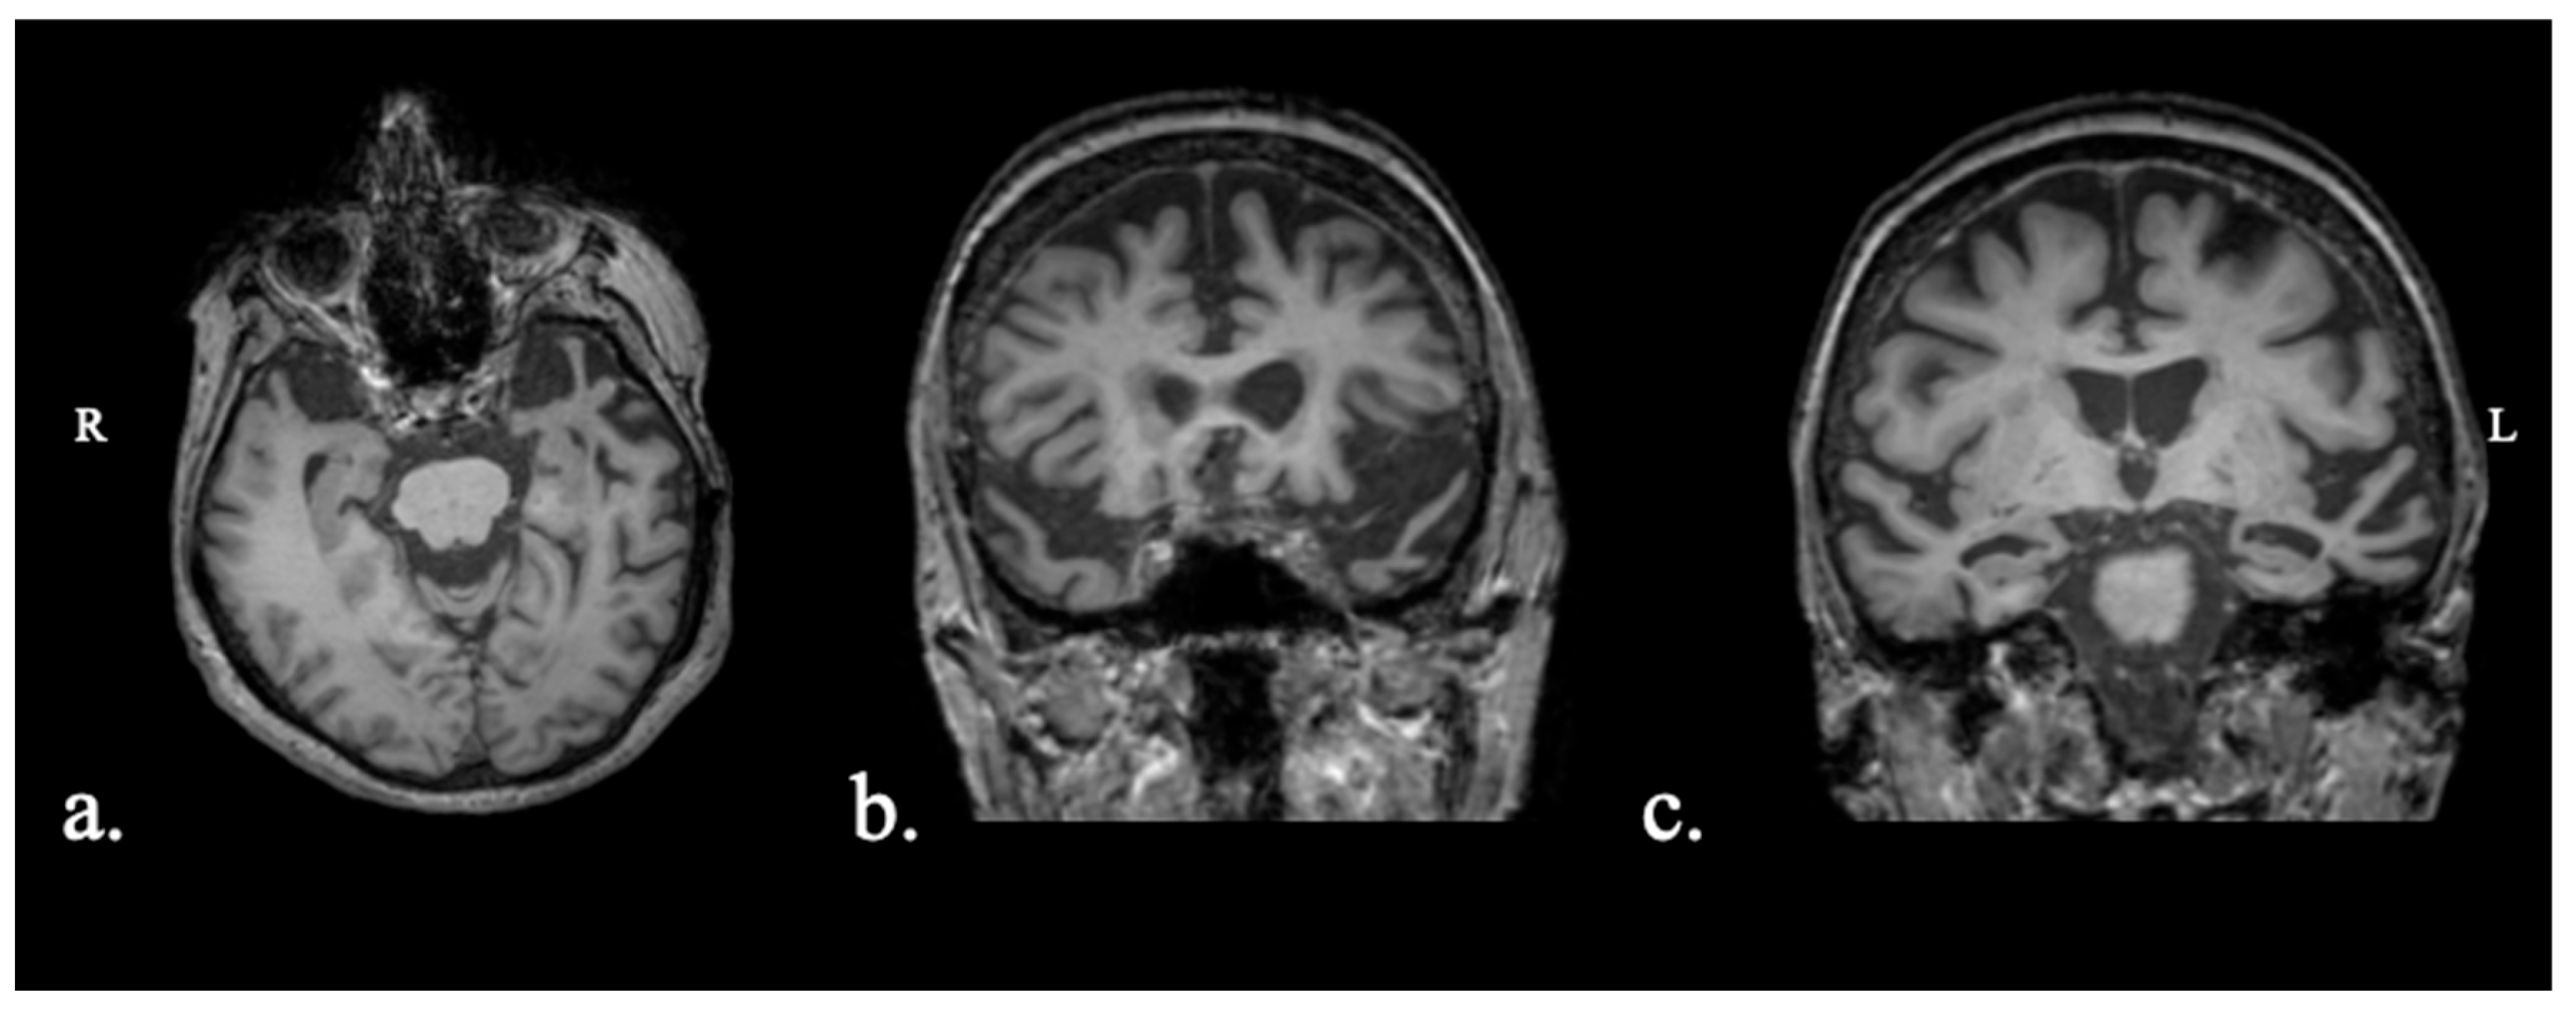

2.1.1. Patient FAY

2.1.2. Patient XTY

2.1.3. Patient ADY

2.1.4. Patient IZS